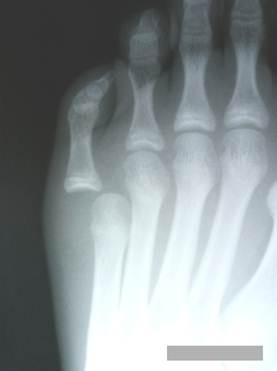

Случай

травматического подвывиха 5 пальца стопы у мальчика 16 лет. Очевидно

повреждение внутренней коллатеральной связки плюсне – фалангового сустава. В

анамнезе травма год назад.